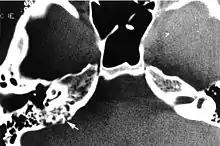

Imaging studies help to identify the tumor and the specific anatomic site of involvement. Magnetic resonance images show a hyperintensity (hypervascularity) of a heterogeneous mass by T1 weighted images. Computed tomography shows a multilocular, lytic destructive temporal bone mass, centered on the vestibular aqueduct (between internal auditory canal and sigmoid sinus).[1][6][7]